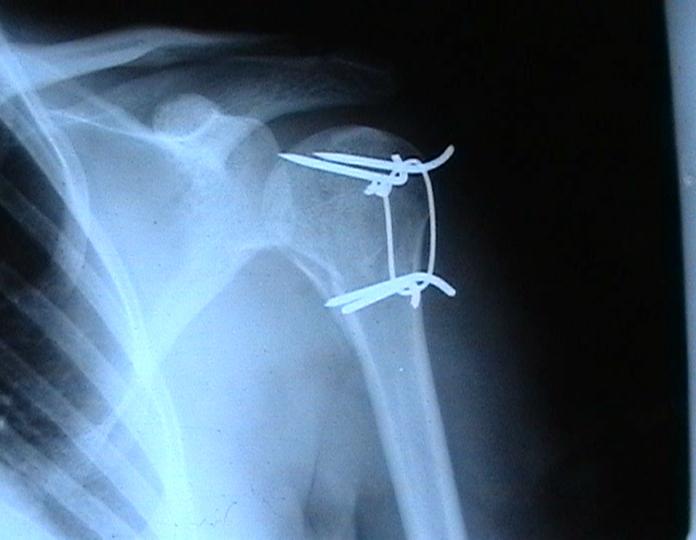

Переломовывих плеча сложная проблема и технически не уверен как для коллег, но для меня сколько я не встречался, технически сложно *вытянуть* вывихнутую головку из-под впадины. Последнее время не применяю пластины для фиксации перелома, а использую спицы и проволочную петлю (тем более часто и густо спонгиозные винты не держатся в головке прочно).

Интересный метод остеосинтеза !

А на сколько он стабилен ?Не происходит ли миграция спиц? Какое количество наблюдений у Вас Евгений? Почему нельзя использовать только проволоку (сформировав для этого туннели в проксимальном и дистальном фрагменте ).

Добавил бы к вашим комментариям ещё - дёшево надежно и мало травматично.

Момент , который следует учитывать при использовании такого рода фиксации - необходимо быть уверенным , что спицы не проникают в сустав, поэтому полезно пользоваться ЭОпом для контроля или интраоперационными рентгенограммами

перед ушиванием раны.

Фиксация получается достаточно стабильная, правда мои заключения основаны только на клинических наблюдениях, возможности протестировать прочность фиксации в лабораторных условиях нет. Я не автор данного типа фиксации в основе его лежит принцип напряженной фиксации (Weber tension Band fixation). Когда-то у нас использовали фиксатор проф Сеппо при переломах

шейки бедра - принцип работы аналогичен, только менее громоздкие элементы конструкции и более доступные для применения в любых условиях.

Не происходит ли миграция спиц?

Я использую обычные 2 мм спицы и пока в 8 случаях , что применял подобную фиксацию миграции не было, хотя вполне вероятна такая возможность и видимо оптимальнее использовать спицы с резьбой на конце, что должно предотвратить потенциальный риск миграции. Хотя если спица начинает пальпироваться под кожей и доставлять неудобство больному, то её легко удалить в условиях перевязочной. На мой взгляд миграция спицы мложет произойти только тогда,

когда пациент начинает активно работать рукой, к этому времени перелом уже срастется, поэтому опасности скомпрометировать стабильность фиксации уже не будет.

Почему нельзя использовать только проволоку (сформировав для этого туннели в проксимальном и дистальном фрагменте ).

Я такой же практик как и Вы, поэтому решать можно или нельзя использовать только проволочную петлю решать Вам, хотя на мой взгляд, обычная проволочная петля не создает многоплоскостной стабильности фиксации, а только лишь в плоскости проведенных отверстий в проксимальном и дистальном фрагментах и другой момент зачастую такие переломы случаются у пожилых людей с порозной костью, тогда, как понимаете, проволочная петля может легко прорезаться через кость и не о какой стабильной фиксации уже речи быть не может в то время как спицы держаться в порозной кости тем более, что при такой фиксации создается момент силы, направленный не на вытягивание спицы из кости.